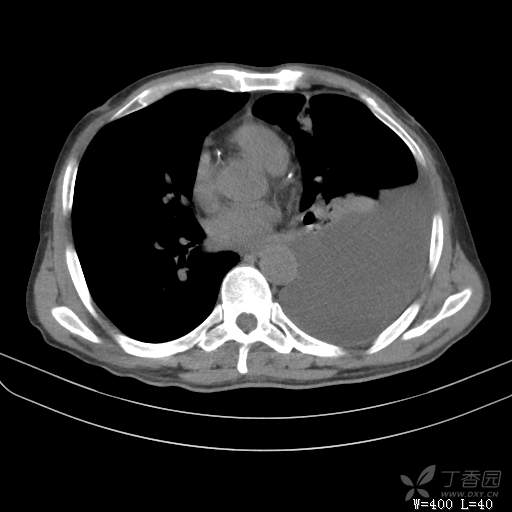

简要病史:胸闷、憋气伴低热1月

体格检查:T:37.6℃;P:92次/分;R:20次/分;Bp:100/60mmHg,神清,呼吸平稳,周身未触及肿大淋巴结,右肺及左上肺叩诊清音,左下肺叩诊浊音,右肺及左上肺呼吸音粗,左下肺未闻及呼吸音,心率92次/分,律齐,无杂音。腹部平坦,软,全腹无压痛,无反跳痛及肌紧张,肝脾肋下未触及,双下肢无水肿。

临床诊断:左侧胸腔积液